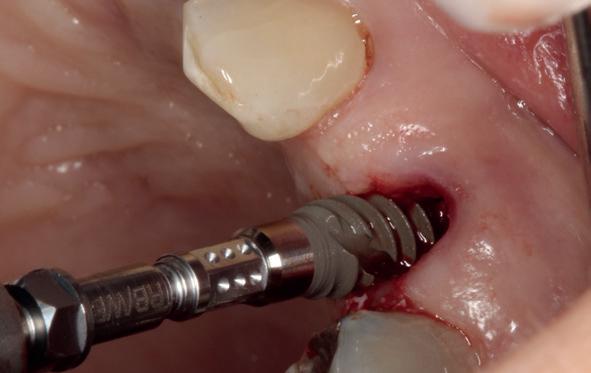

Afbeelding 1 en 2. Een immediate placement (afbeelding 1) is maar weinig invasief en zal weinig nalast geven. Bij een uitgebreide botopbouw (afbeelding 2) daarentegen is de wond veel groter en kan er meer nalast verwacht worden.

In deze casus is extractie van de 37 geïndiceerd in verband met een fistel en restpockets, zoals zichtbaar op de röntgenfoto’s (afbeelding 1). Duidelijk te zien is de forse peri-apicale ontsteking en het botverlies bij de 37, dat zowel richting buccaal als linguaal doorloopt. De 37 wordt atraumatisch verwijderd. Er is aan de linguale zijde veel bot verloren en er is sprake van een perforatie aan de buccale zijde.

Er wordt besloten om botmateriaal te plaatsen in de extractie-alveole. Vervolgens wordt het afgesloten met een titanium versterkt d-PTFE membraan (afbeelding 2). Na vier weken wordt het membraan verwijderd.

Zes maanden na extractie wordt het implantaat 37 geplaatst. Er is sprake van een goede genezing en de processushoogte en -breedte zijn behouden en opgebouwd. Ook is er zichtbaar gekeratiniseerd weefsel

gewonnen. De wond kan na het plaatsen van een healing abutment primair gesloten worden (Afbeelding 3a-3d).